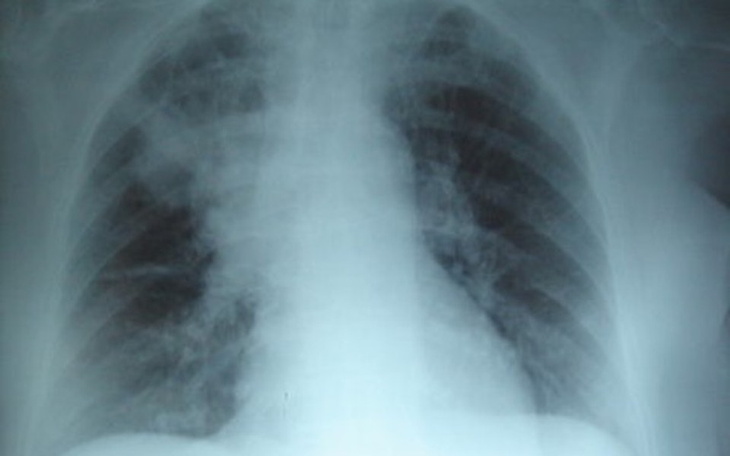

Kasia,choruje na mukowiscydoze.Choroba ta utrudnia normalne funkcjonowanie.Zmierza się z nią codziennie,nie myśląc o niczym innym.To straszne,ile trzeba mieć w sobie siły i samozaparcia do pokonywania jej z dnia na dzień.Wierzymy,że uda nam sie,dzięki pieniążkom zebranym,Kasia na chwile zapomni o ciężkiej chorobie.Dziekujemy za każde datki.